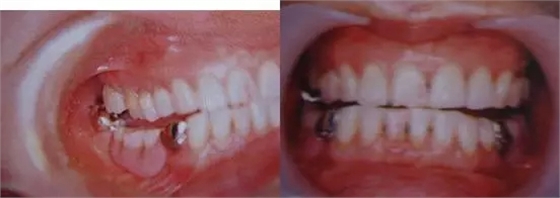

640.webp (8).jpg

圖9.上頜和下頜第二磨牙中發(fā)生的前方誘導(dǎo)干擾引發(fā)的張口困難。

下頜磨牙的遠(yuǎn)中頰側(cè)牙尖的近中頰側(cè)斜面和上頜磨牙的近中頰側(cè)牙尖的遠(yuǎn)中腭側(cè)斜面相接觸。

640.webp (9).jpg

圖10.不考慮下頜第三磨牙的咬合平面破壞的修復(fù)體制作完成后,后方磨牙干擾引發(fā)的前方誘導(dǎo)干擾。